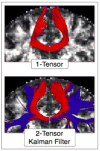

Mild traumatic brain injury (mTBI), also referred to as concussion, remains a controversial diagnosis because the brain often appears quite normal on conventional computed tomography (CT) and magnetic resonance imaging (MRI) scans. Such conventional tools, however, do not adequately depict brain injury in mTBI because they are not sensitive to detecting diffuse axonal injuries (DAI), also described as traumatic axonal injuries (TAI), the major brain injuries in mTBI. Furthermore, for the 15 to 30 % of those diagnosed with mTBI on the basis of cognitive and clinical symptoms, i.e., the "miserable minority," the cognitive and physical symptoms do not resolve following the first 3 months post-injury. Instead, they persist, and in some cases lead to long-term disability. The explanation given for these chronic symptoms, i.e., postconcussive syndrome, particularly in cases where there is no discernible radiological evidence for brain injury, has led some to posit a psychogenic origin. Such attributions are made all the easier since both posttraumatic stress disorder (PTSD) and depression are frequently co-morbid with mTBI. The challenge is thus to use neuroimaging tools that are sensitive to DAI/TAI, such as diffusion tensor imaging (DTI), in order to detect brain injuries in mTBI. Of note here, recent advances in neuroimaging techniques, such as DTI, make it possible to characterize better extant brain abnormalities in mTBI. These advances may lead to the development of biomarkers of injury, as well as to staging of reorganization and reversal of white matter changes following injury, and to the ability to track and to characterize changes in brain injury over time. Such tools will likely be used in future research to evaluate treatment efficacy, given their enhanced sensitivity to alterations in the brain. In this article we review the incidence of mTBI and the importance of characterizing this patient population using objective radiological measures. Evidence is presented for detecting brain abnormalities in mTBI based on studies that use advanced neuroimaging techniques. Taken together, these findings suggest that more sensitive neuroimaging tools improve the detection of brain abnormalities (i.e., diagnosis) in mTBI. These tools will likely also provide important information relevant to outcome (prognosis), as well as play an important role in longitudinal studies that are needed to understand the dynamic nature of brain injury in mTBI. Additionally, summary tables of MRI and DTI findings are included. We believe that the enhanced sensitivity of newer and more advanced neuroimaging techniques for identifying areas of brain damage in mTBI will be important for documenting the biological basis of postconcussive symptoms, which are likely associated with subtle brain alterations, alterations that have heretofore gone undetected due to the lack of sensitivity of earlier neuroimaging techniques. Nonetheless, it is noteworthy to point out that detecting brain abnormalities in mTBI does not mean that other disorders of a more psychogenic origin are not co-morbid with mTBI and equally important to treat. They arguably are. The controversy of psychogenic versus physiogenic, however, is not productive because the psychogenic view does not carefully consider the limitations of conventional neuroimaging techniques in detecting subtle brain injuries in mTBI, and the physiogenic view does not carefully consider the fact that PTSD and depression, and other co-morbid conditions, may be present in those suffering from mTBI. Finally, we end with a discussion of future directions in research that will lead to the improved care of patients diagnosed with mTBI.